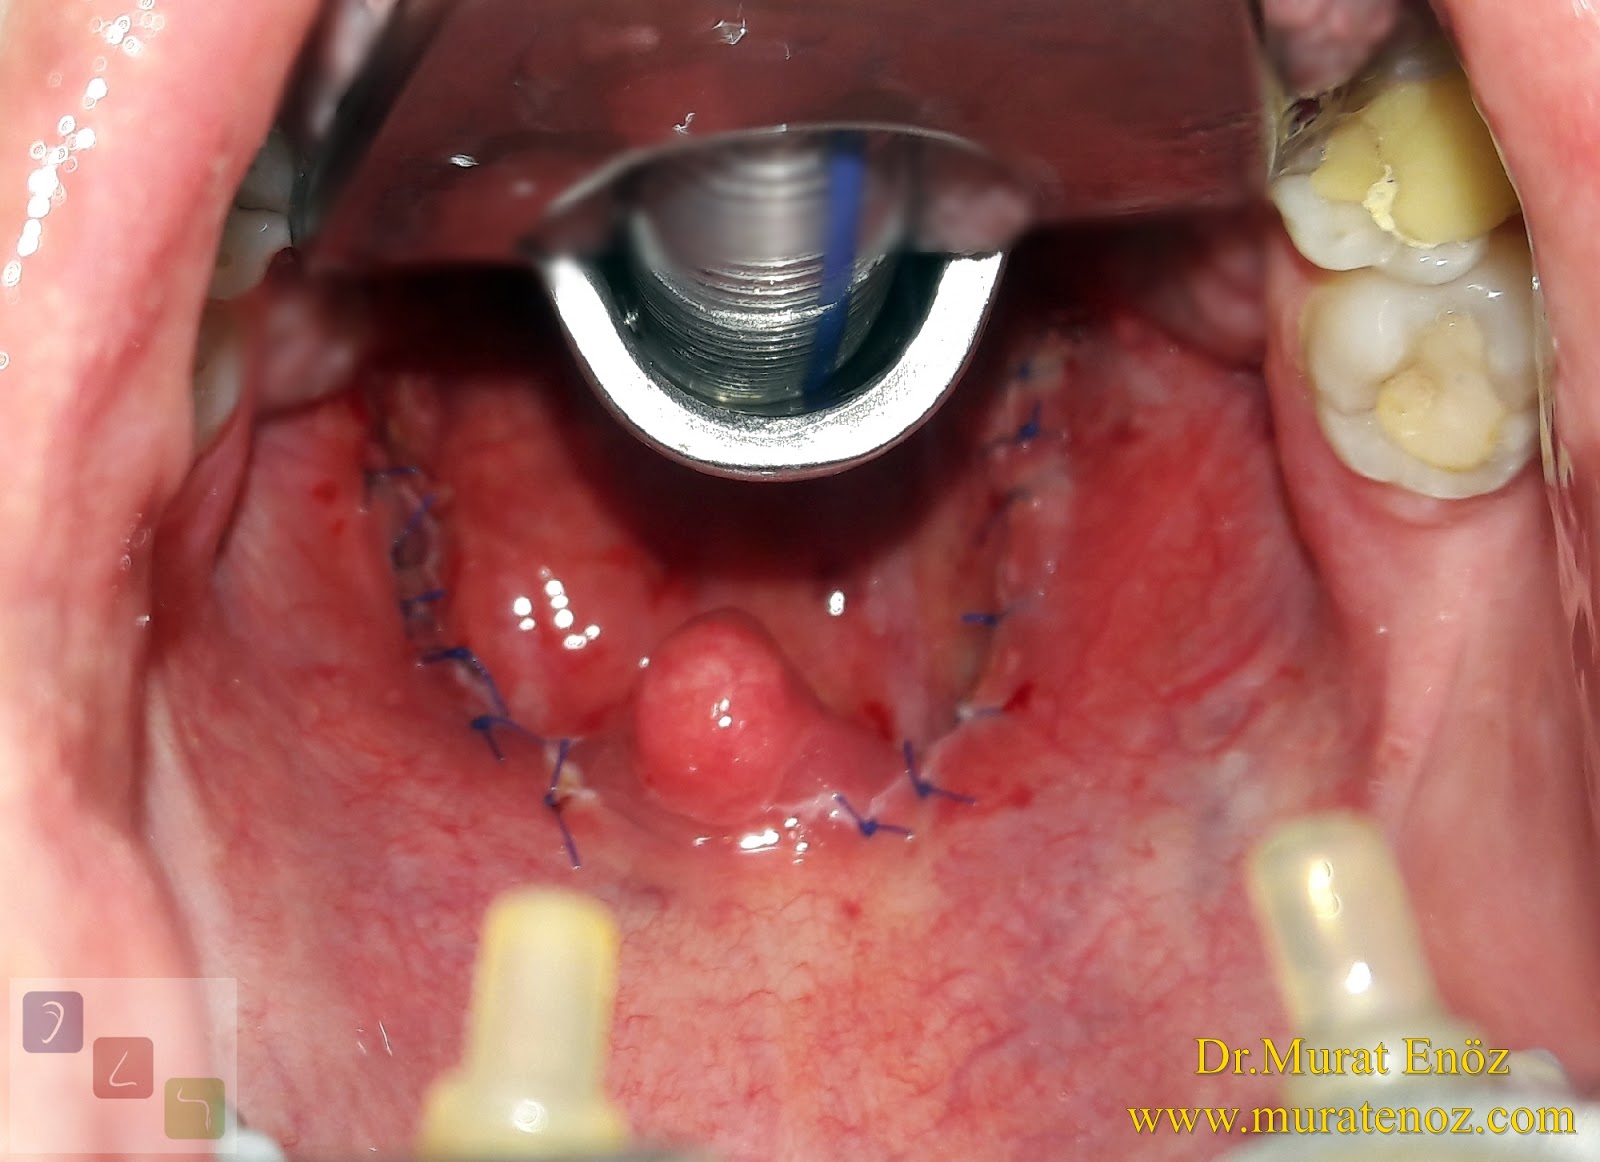

Thermal Welding Sistemi Ile Bademcik Ameliyati Ve Klasik Geniz Eti Ameliyati Oncesi Sonrasi Fotograflari

Thermal Welding Ile Agrisiz Kanamasiz Bademcik Ameliyati

Kismi Parsiyel Tonsillektomi Tonsillotomi Ve Tam Bademcik Ameliyati